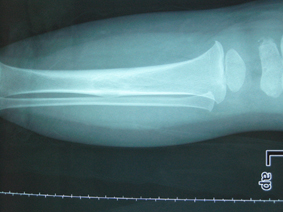

以下是引用黑白光影在2008-12-17 21:57:00的发言:[br]考虑骨纤维异常增殖症,不排除非骨化纤维瘤。

以下是引用zsl6918在2008-12-18 4:25:00的发言:[br]考虑骨纤可能性大